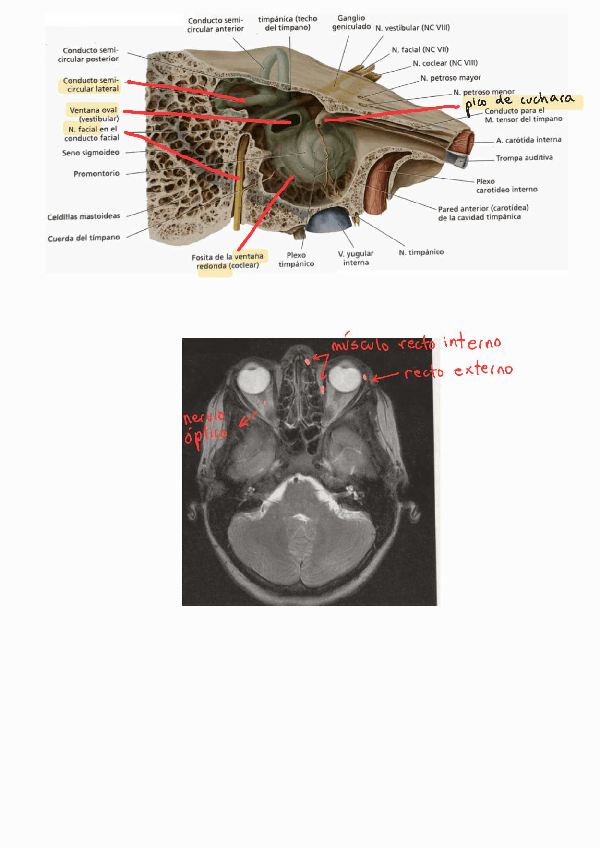

EXAMEN NEUROANATOMÍA DICIEMBRE 2023

He publicado nuevos apuntes de 2º Anatomía Humana: Estesiología y Sistema Nervioso: EXAMEN NEUROANATOMÍA DICIEMBRE 2023

PREGUNTAS-CORTAS-EXAMEN-NEUROANATMIA-DICIEMBRE-2023.pdf

IMAGENES-EXAMEN-NEUROANATOMIA-DICIEMBRE-2023.pdf

CASOS-CLINICOS-EXAMEN-NEUROANATOMIA-DICIEMBRE-2023.pdf